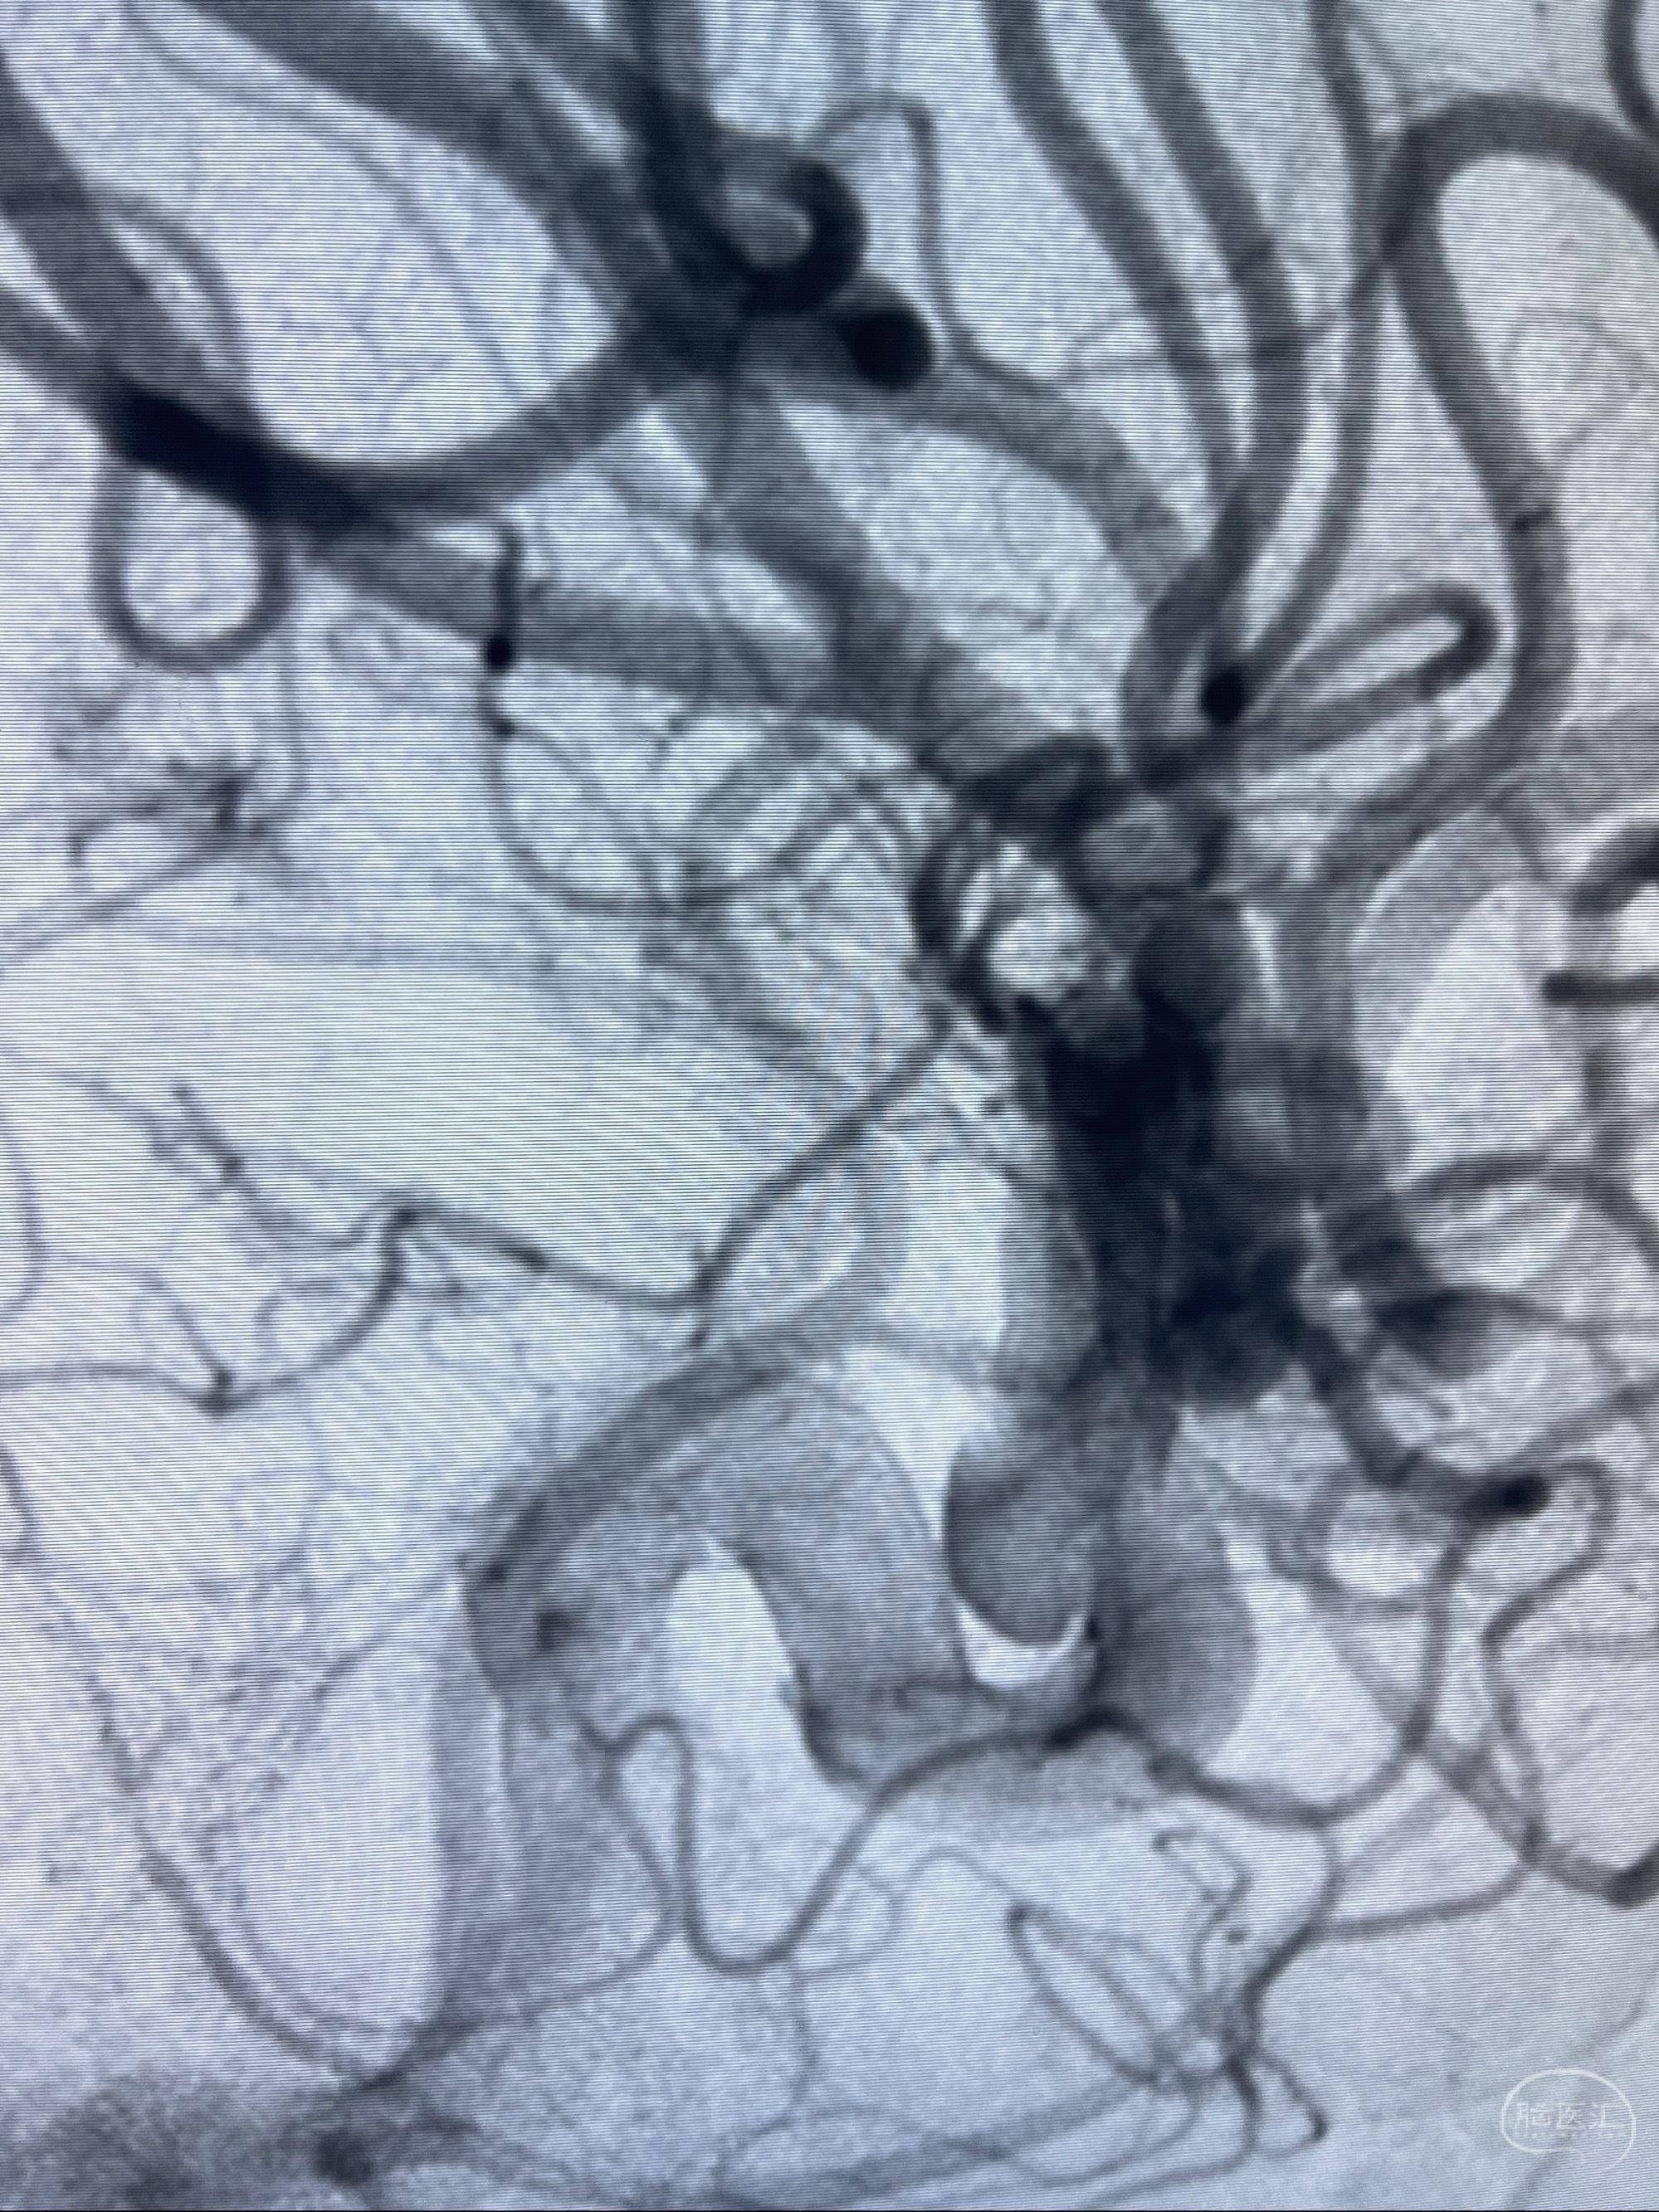

2023-07-27全脑血管造影:双侧颈内动脉眼动脉段动脉瘤,右侧较大

2023-08-01全麻下行双侧颈眼动脉瘤支架辅助栓塞

手术顺利,麻醉苏醒佳,遵嘱动作

术后即刻CT